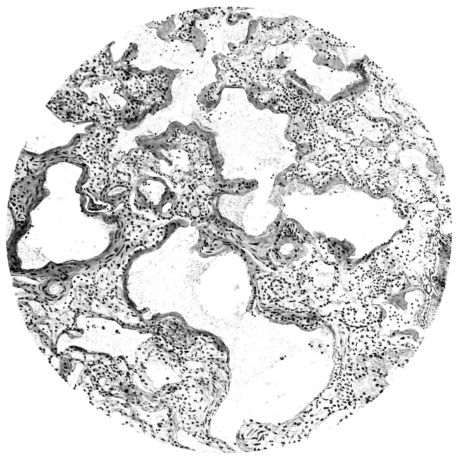

FIG. III. AUTOPSY NO. 90. DRAWING FROM A LESION OF THE TRACHEA (SOMEWHAT OLDER THAN THAT ILLUSTRATED IN FIGURE II). THE MUCOSA IS ENTIRELY LACKING. CONGESTION AND EDEMA ARE THE STRIKING FEATURES IN THE SUBMUCOSA. THE NECROTIZING PROCESS HAS EXTENDED INTO THE MUCUS GLANDS. THIS IS SHOWN IN THE LOWER PICTURE.

FIG. IV. AUTOPSY NO. 205. CONGESTION AND EDEMA OF THE SUBMUCOSA AND REGENERATION OF THE TRACHEAL EPITHELIUM.

FIG. VII. AUTOPSY NO. 94. A NECROTIZING PROCESS LIKE THAT OF THE TRACHEA ILLUSTRATED IN FIGURE II. HERE IT IS SHOWN TO INVOLVE THE WALL OF THE BRONCHIOLE.

FIG. V. AUTOPSY NO. 95. AN EARLY LESION OF THE BRONCHIOLE CHARACTERIZED BY HYALINIZATION OF THE EPITHELIUM AND SEROUS EXUDATE IN THE LUMEN.

FIG. VI. AUTOPSY NO. 103. ILLUSTRATES ANOTHER EARLY BRONCHIOLAR LESION. THE EPITHELIUM IS LACKING, THE CONGESTED VESSELS OF THE SUBMUCOSA PROTRUDE INTO THE LUMEN WHICH CONTAINS DESQUAMATED EPITHELIUM, MUCUS, AND RED BLOOD CELLS.

The changes are less marked, perhaps, in the trachea than in its finer ramifications. The mucosa is constantly more or less destroyed and large areas, usually focal, are entirely devoid of their epithelial covering. This is replaced by a sparse exudate, composed largely of red blood cells, mucus, a small amount of fibrin, and nuclear fragments (Fig. II). It may dip into the submucosa for a short distance, but usually these indentures are associated with the ducts of the mucous glands into which the inflammatory reaction extends. A more striking feature than the exudate, however, is the edema and the congestion of the submucosa. The loose areolar tissue of the submucosa is spread widely apart, and throughout it distended blood vessels are very conspicuous. Occasionally such a vessel is broken and actual hemorrhage appears in the submucosa. Occasionally, too, the inflammation extends down the duct to the mucous gland itself, and here, also, aplastic inflammatory reaction is evident, inasmuch as the acini now stain intensely red with the cells undifferentiated from each other and specked here and there by broken remains of the dead nuclei (Fig. III). After the disease has continued for a short period, even at the end of five or six days, some regeneration of the epithelial lining may be seen (3) (Fig. IV). But despite this, the acute picture persists, and there goes on, side by side, an attempted repair characterized by epithelial regeneration and the same evidence of acute change. Since the lesion is essentially a superficial one, scars or contractures of any extent are not encountered in the trachea, even in examples of the disease that have ended fatally only after many weeks.[4]

15There is considerable evidence to support the view that the disease spreads from bronchus to bronchus, and in keeping with this view, various stages in the inflammatory processes are more readily determined in these smaller structures than in the trachea. Furthermore, it must be emphasized that even the mildest and the most extreme of these stages are not infrequently encountered in the same lung. The earliest lesion is manifested by an increased homogeneity of the protoplasm of the epithelial lining of the bronchus. The cell protoplasm loses its normal granulation and the nucleus, somewhat darker than usual, becomes conspicuous on a red base (Fig. V). In the lumen of such a tube a serous exudate, perhaps mixed with mucus, is encountered, and there is some spreading apart of the surrounding muscular tissue with engorgement of the vessels. This picture merges gradually into one where the epithelium appears as a homogeneous, red-staining ribbon, devoid of nuclei, often exfoliated, in part at least, from the underlying submucosa (92). The change is traceable through the larger bronchi, even to the ducti alveolares, and not infrequently, bacteria, either as a diffuse, minute dotting or in the form of circumscribed, colony-like formations, are spread through the red, ribbon-like strand (Fig. XVI). With the exfoliation of the epithelial lining, the submucous vessels become more and more conspicuous and may bulge into the lumen of the tube (Fig. VI). That they actually weep into the lumen is proved by the presence of red blood cells in the exudate, now rich in mucus, broken-down nuclei, and desquamated cells. The necrotizing process may not extend deeper than the epithelial lining as is the status described above (140, 162), but it also frequently involves the underlying submucous and muscular layers, so that these lose their identity and stand out as homogeneous masses, in which fragmented nuclei and bacterial accumulations are prominent. Such deeper necrotizing areas may be focal (Fig. VII), or may involve the entire circumference of the tube (Fig. VIII). Occasionally, the epithelium, now dead and staining homogeneously, is lifted from the underlying submucosa in the form of a blister (66), and has very much the same appearance as the well known, early reaction which follows the application of croton oil to the rabbit’s ear. Where this occurs, the submucosa is less involved, as though the necrotizing agent had not penetrated to the same depth and the serous reaction beneath were actually a beneficent exudate. These blisters are in contrast with the deeper areas where the fibrinous mass, mixed with the dead tissue, forms an intensely staining ring or band, which extends through the bronchiolar wall even to the surrounding alveoli.